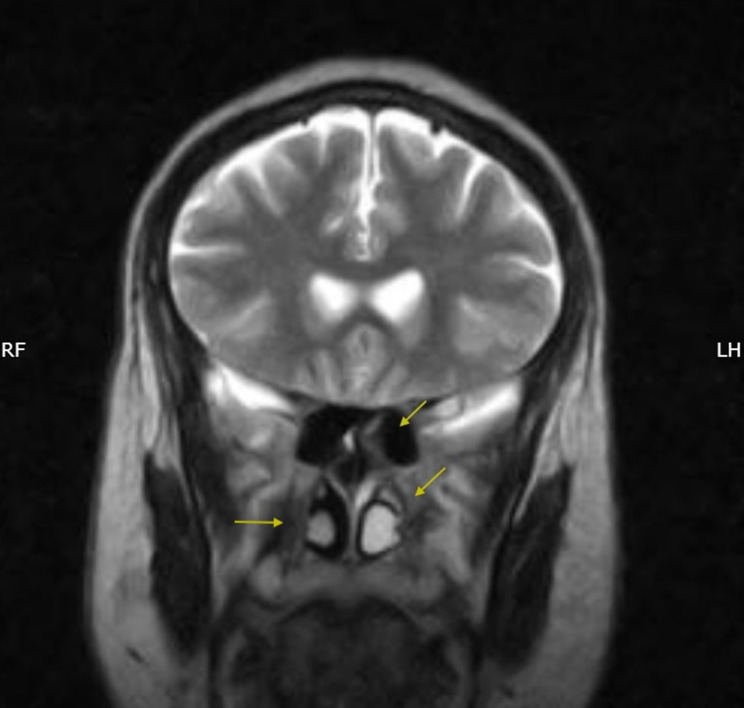

脑脊液(CSF)鼻漏是一种罕见但严重的疾病,最常见于颅底创伤或手术,其表现为癫痫的并发症极为罕见。癫痫管理的重点是癫痫发作控制和预防即时并发症,如癫痫持续状态或跌倒相关损伤。我们描述了一位36岁的男性局灶性癫痫患者,经磁共振成像和β-2转铁蛋白检测证实,他出现了反复发作的脑脊液鼻漏,并伴有暂时性的夜间惊厥和癫痫相关的筛板缺损。我们假设在这些癫痫发作期间反复的轻微颅脑损伤和短暂的颅内压激增导致了颅底缺损。系统地排除了所有其他病因;虽然不能证明明确的因果关系,但强烈的时间关联支持了这一假设。通过内窥镜手术修复成功解决了脑脊液泄漏,并实施了包括改变睡眠安排在内的预防措施。该病例强调了考虑脑脊液渗漏的重要性,癫痫患者出现不明原因的鼻分泌物,强调需要加强癫痫发作管理,及时识别和多学科护理,以防止并发症。

Cerebrospinal fluid (CSF) rhinorrhea is a rare but serious condition that most commonly follows skull-base trauma or surgery, and its manifestation as a complication of epilepsy is exceptionally rare. Epilepsy management focuses on seizure control and prevention of immediate complications, such as status epilepticus or fall-related injuries. We describe a 36-year-old male with focal-onset epilepsy who developed recurrent CSF rhinorrhea temporally associated with nocturnal convulsions and a seizure-related cribriform-plate defect confirmed by magnetic resonance imaging and β-2 transferrin testing. We hypothesize that repeated minor cranial trauma and transient intracranial pressure surges during these seizures precipitated the skull-base defect. All alternative etiologies were systematically excluded; although a definitive causal link cannot be proven, the strong temporal association supports this hypothesis. The CSF leak was successfully addressed through endoscopic surgical repair, and preventive measures, including alterations to sleeping arrangements, were implemented. This case underscores the importance of considering CSF leakage in individuals with epilepsy presenting with unexplained nasal discharge, highlighting the need for enhanced seizure management, prompt recognition, and multidisciplinary care to prevent complications.